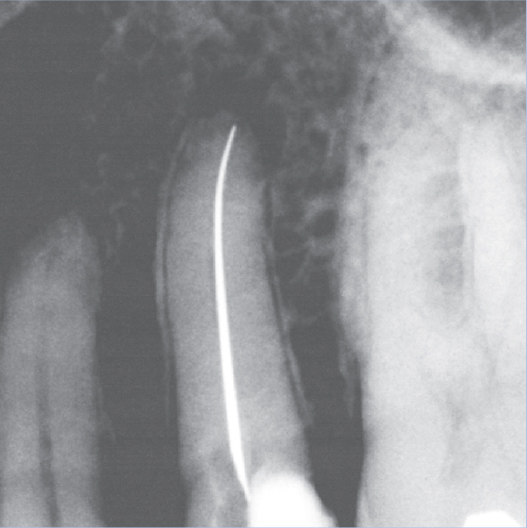

Before

Before Root Canal treatment